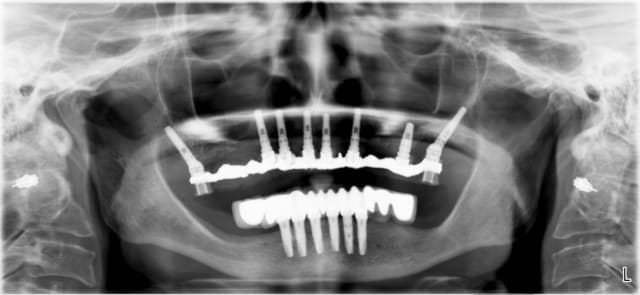

Maintenant voilà un cas réalisé(ressemblant au tien je pense); avec la pano avant et la pano à trois mois! La patiente est ressortie du cabinet 5 heures après avec ses dents. J'ai fait refaire un scan à la patiente pour avoir la position des implants et faire la comparaison entre la planif et le travail executé.

Je vais entendre hurler pxav car les implants ont été mis en distraction osseuse je dirai plutot en condensation... bref. A vous de voir!